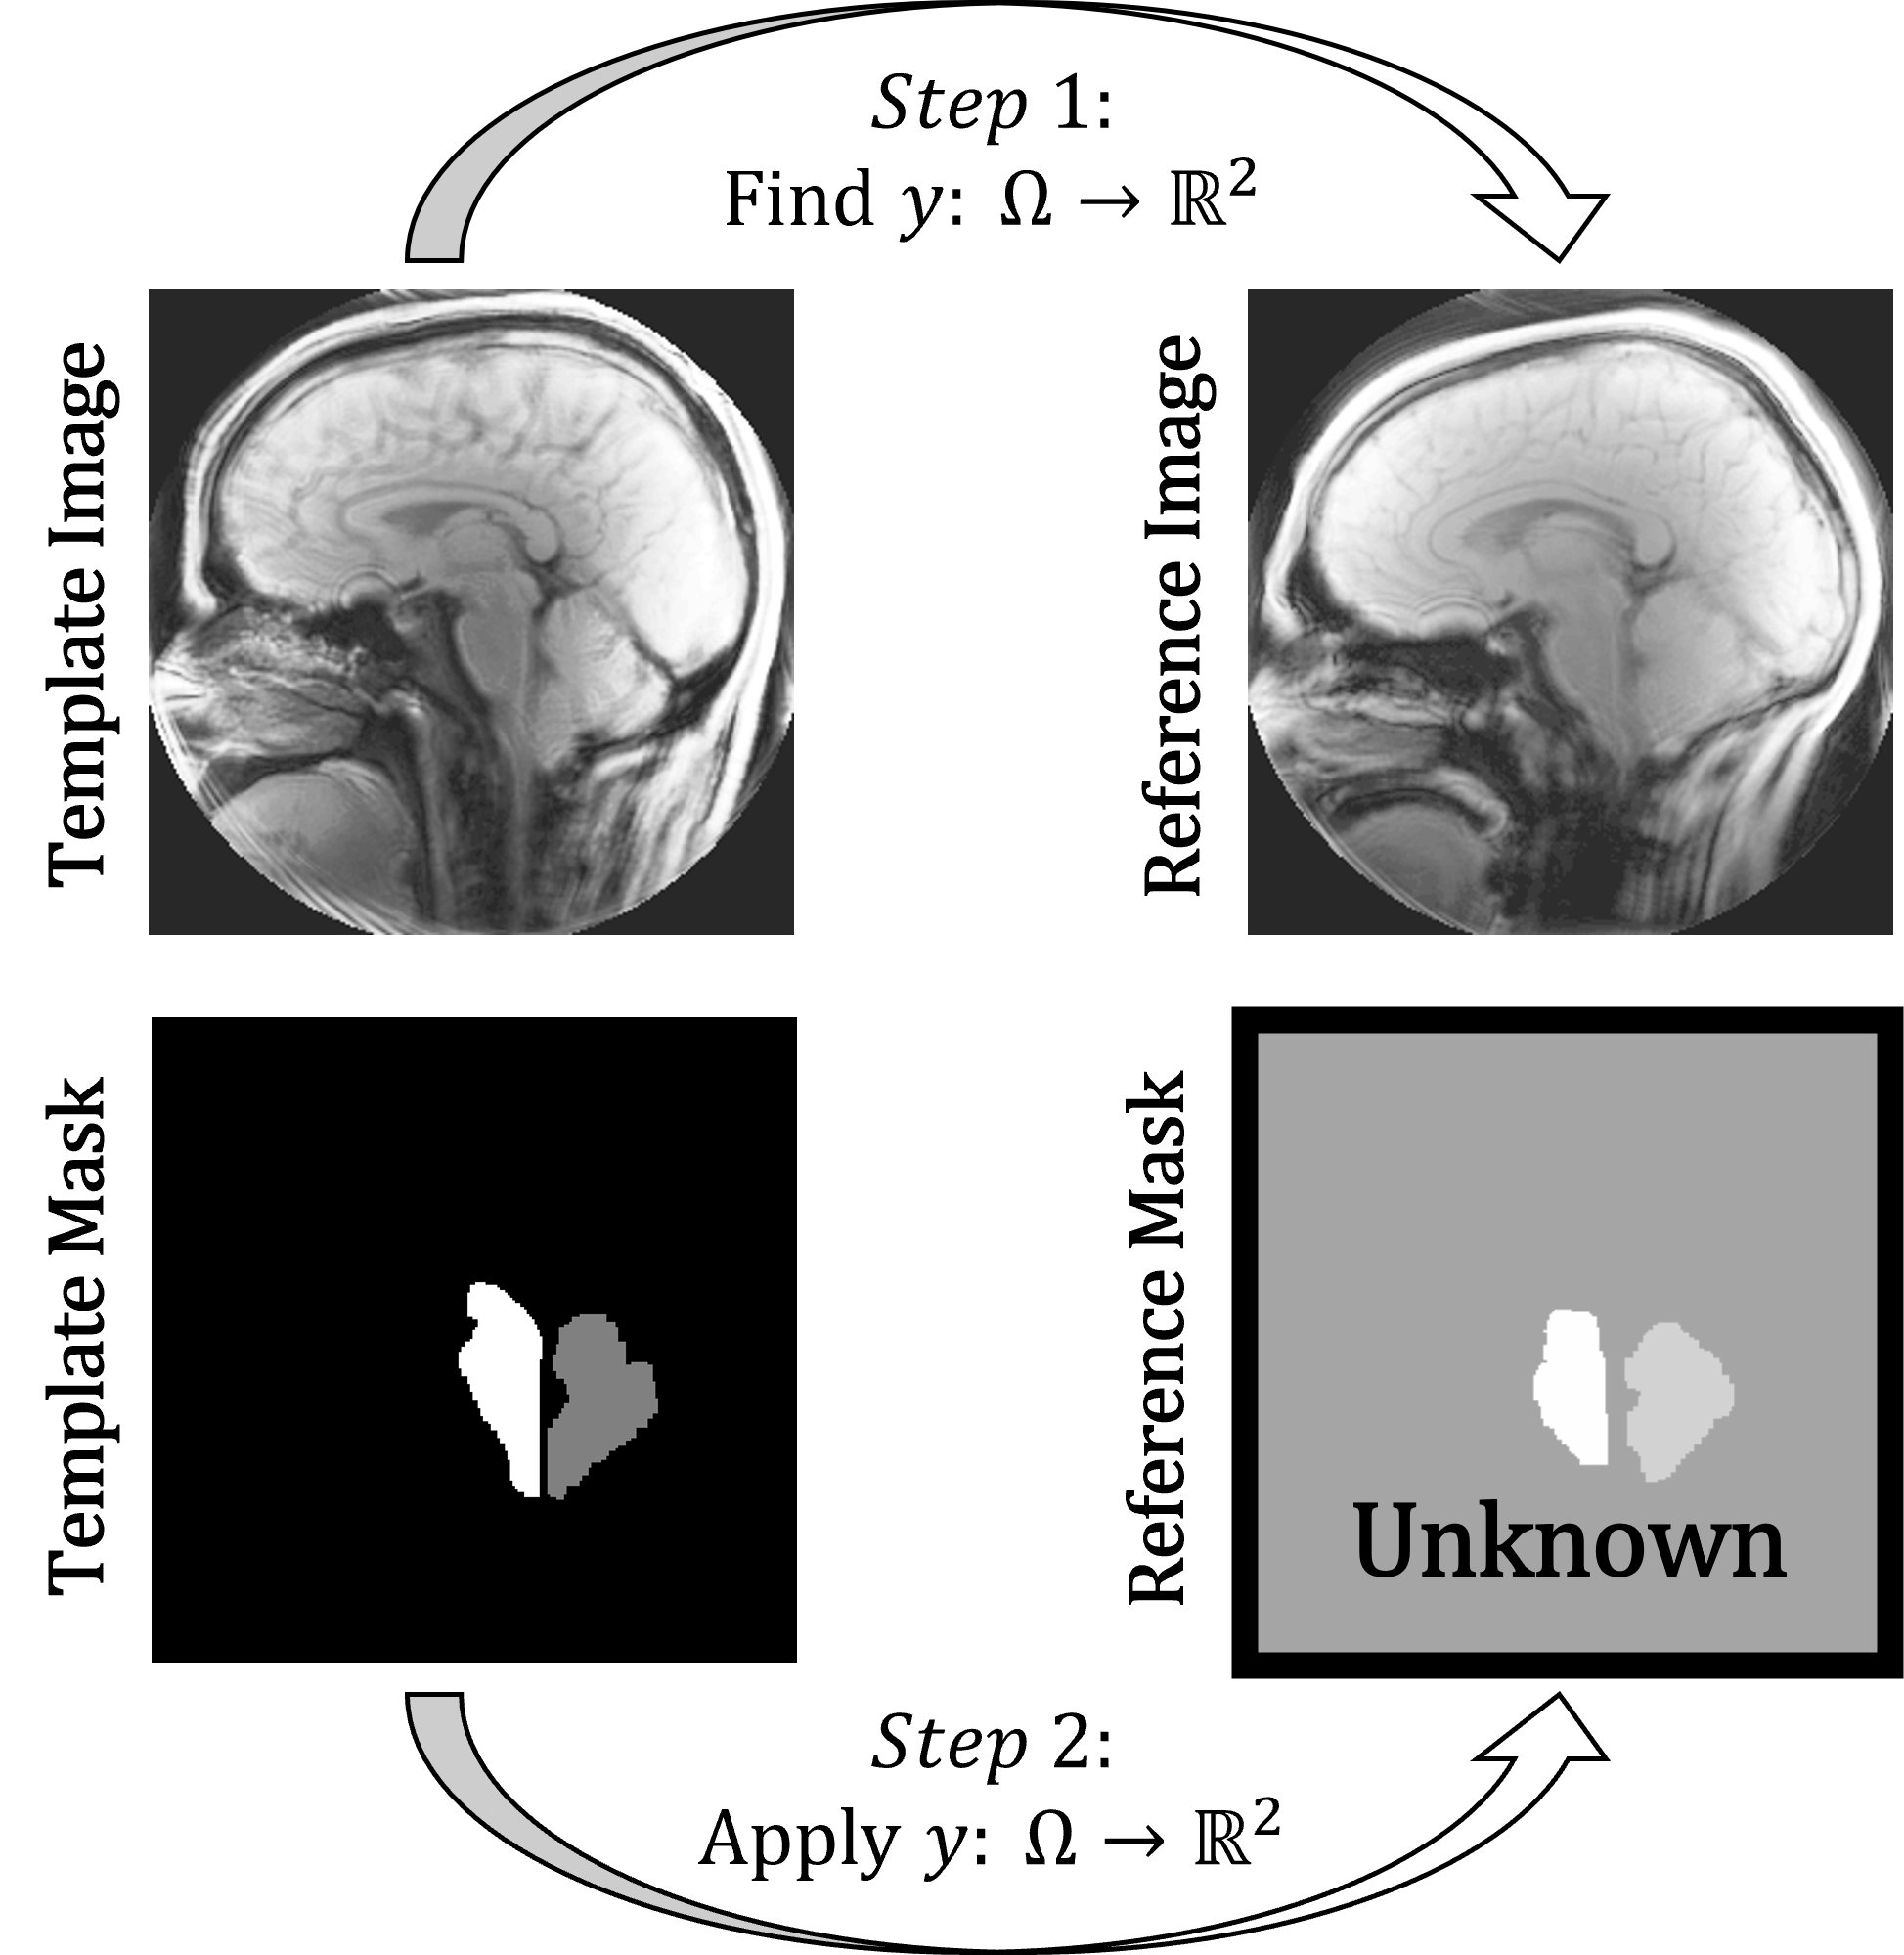

In investigating atlas-based image registration, our study builds on methods from a MATLAB toolbox called FAIR [9]. Image registration from this toolbox relies on the idea of a template image and a reference image. In the case of segmenting MR images, the reference is the magnitude image (described further in Section 2.1) that needs segmentation and the template is some magnitude image that has already been segmented. The main idea of this approach is to find a transformation that approximately aligns the template image to the reference.

Given a new image without a mask, our method compares the new image to a set of 51 labeled images in order to predict a mask for the new image. To allow for a pixel-to-pixel comparison, we solve a set of registration problems. Following the language used in FAIR, the new image is called the reference, while the known labeled images are templates.

Here, we discuss how templates are chosen to be compared to new references along with an averaging method to reduce outlying results, and in the next section we will describe the registration performed in each of these comparisons.